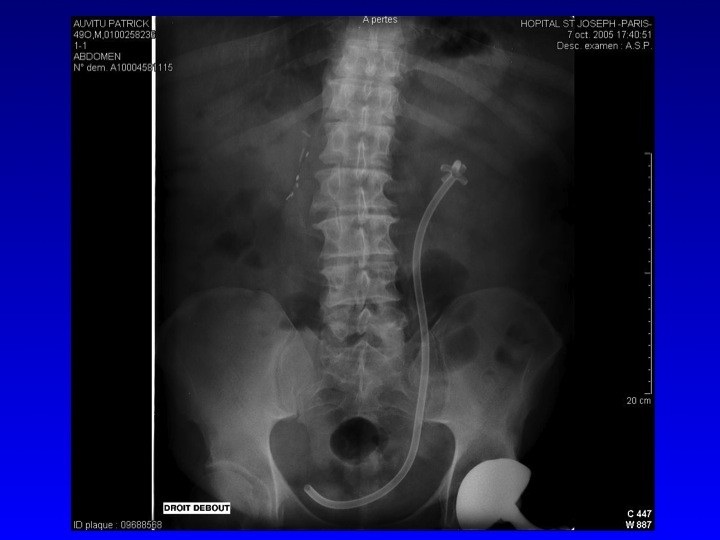

Prise en charge des petites tumeurs rénales en 2011 : diaporama 1